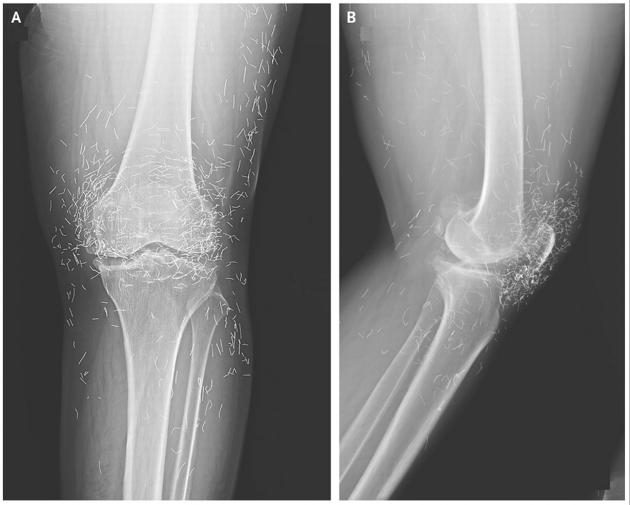

Сотни маленьких игл, используемых в иглоукалывании